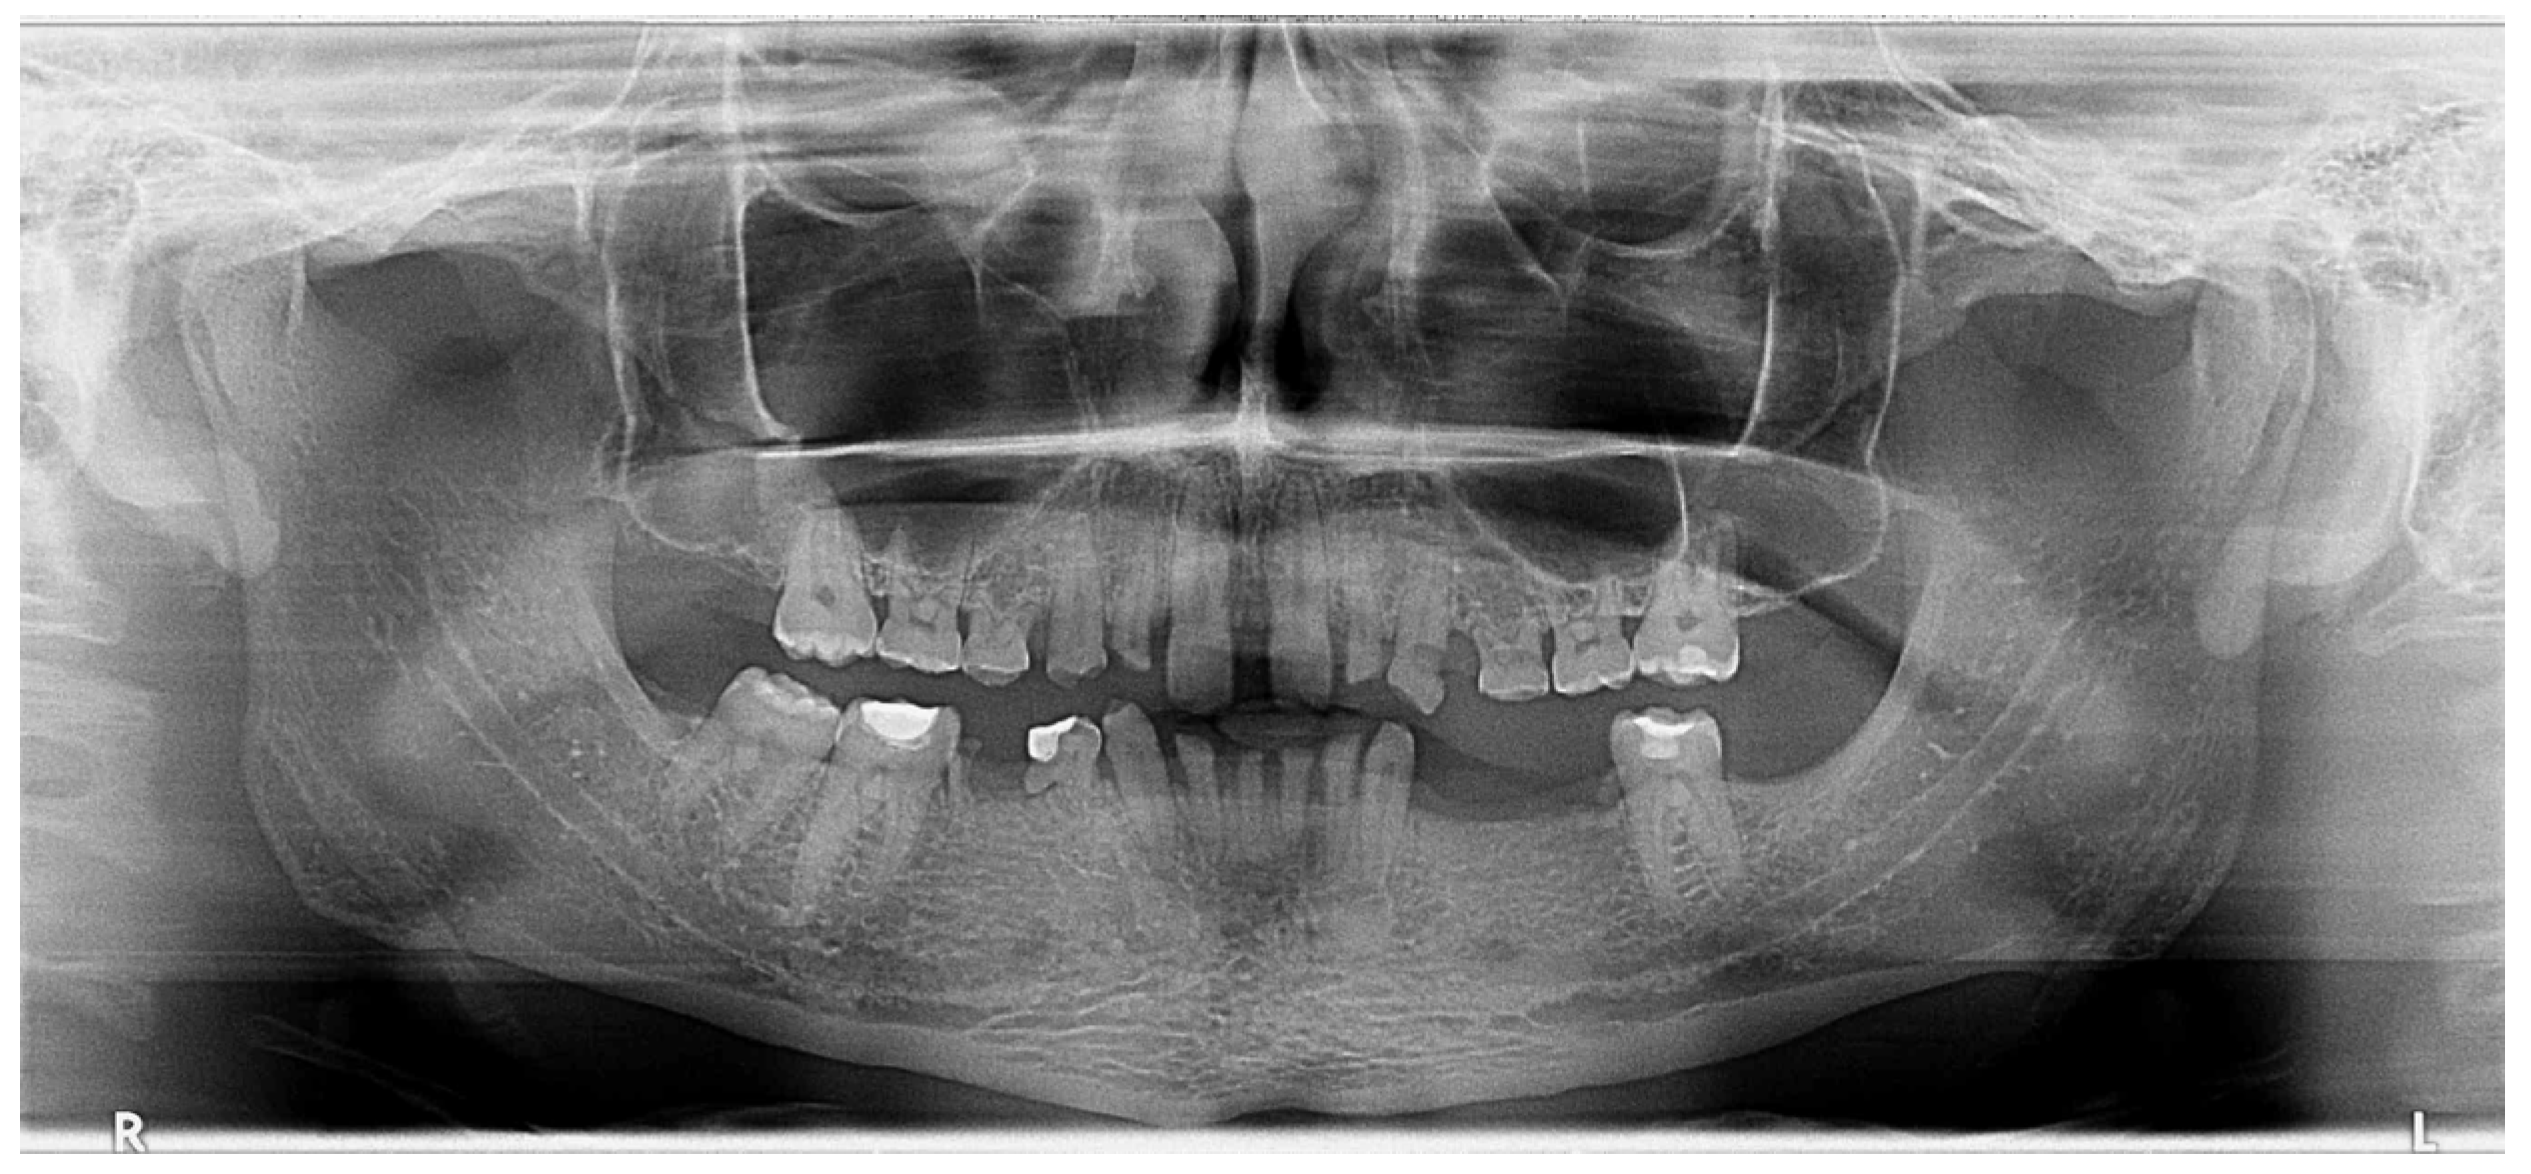

Figure 4.

OPG. Radiographic initial situation of the patient. The radiograph reveals the presence of 7 permanent teeth on the dental arches.

Radiographic examination did not reveal periapical alteration of the present teeth and excluded the diagnosis of dental impaction (Figure 4).